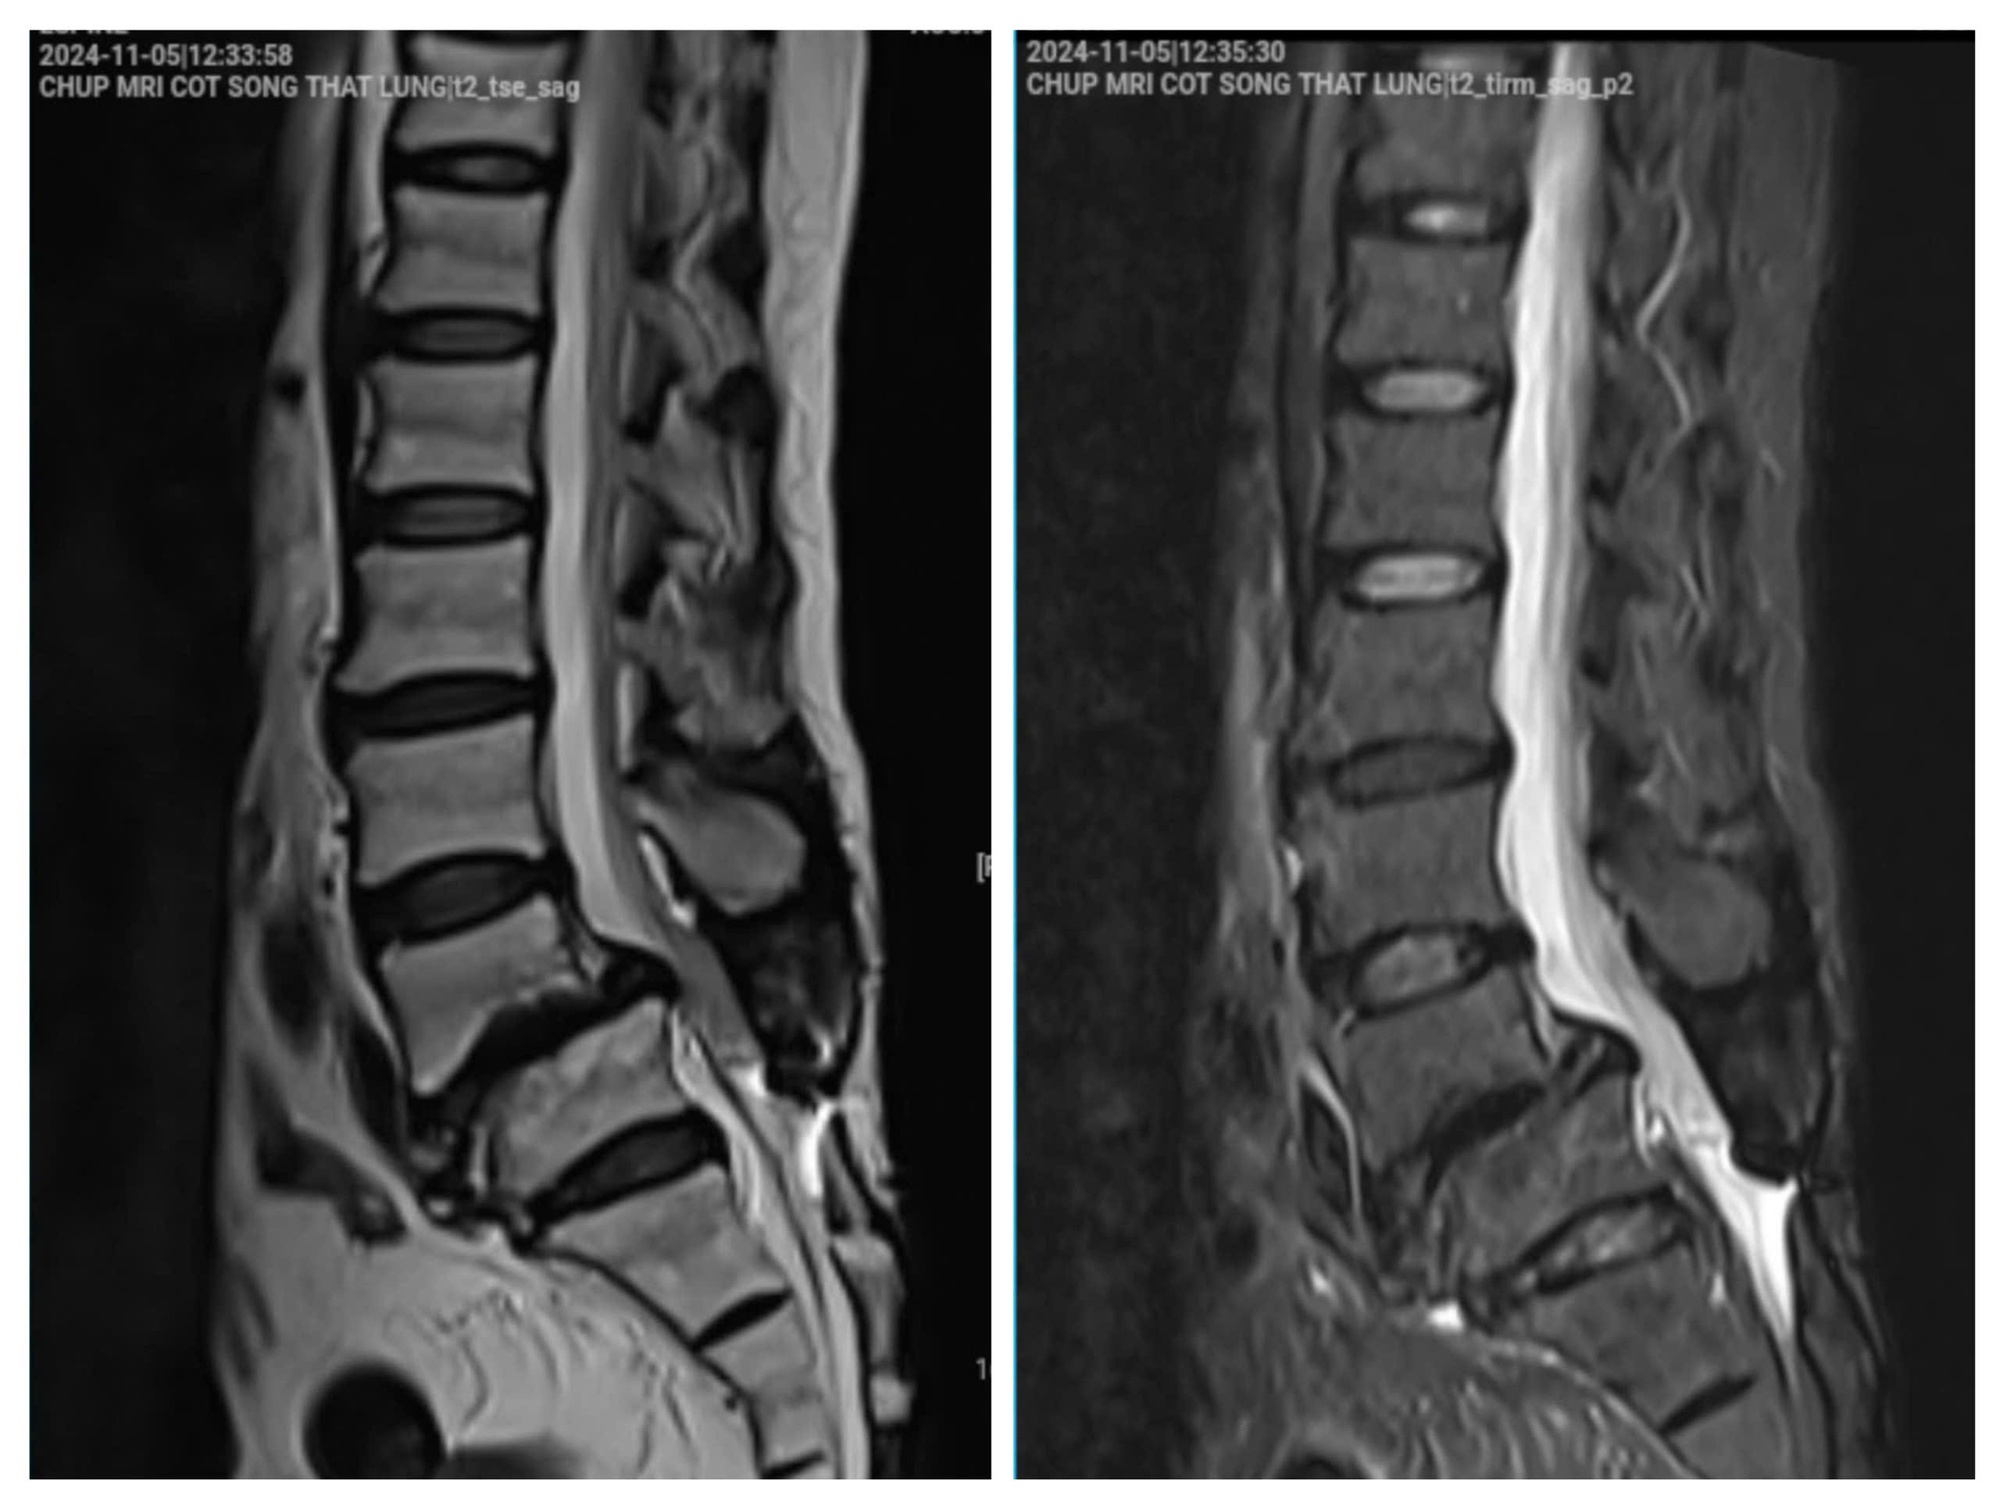

Hình ảnh phim chụp của bệnh nhân vào tháng 11/2024. (Ảnh: BSCC)

Theo BS Cao Thanh Phong, hình ảnh cận lâm sàng cho thấy:

- Hở eo và trượt đốt sống L4 ra trước độ II

- Thoát vị đĩa đệm L4/L5 ra sau, có phần di trú

- Hẹp ống sống nặng, đường kính trước - sau <7mm

- Hẹp ngách bên, lỗ tiếp hợp, chèn ép toàn bộ rễ thần kinh ngang mức L4 và L5

Không dừng lại ở đó, bệnh nhân còn có phình đĩa đệm tại nhiều tầng khác như L2/L3, L3/L4 và L5/S1, gây chèn ép bao màng cứng và hẹp ống sống mức độ nhẹ.

Đặc biệt, bệnh nhân đã xuất hiện dấu hiệu rối loạn cơ tròn, tổn thương chùm thần kinh đuôi ngựa và thần kinh tọa.

Theo BS Cao Thanh Phong, đây là dấu hiệu nguy hiểm, nếu chậm trễ có thể để lại di chứng thần kinh không hồi phục.